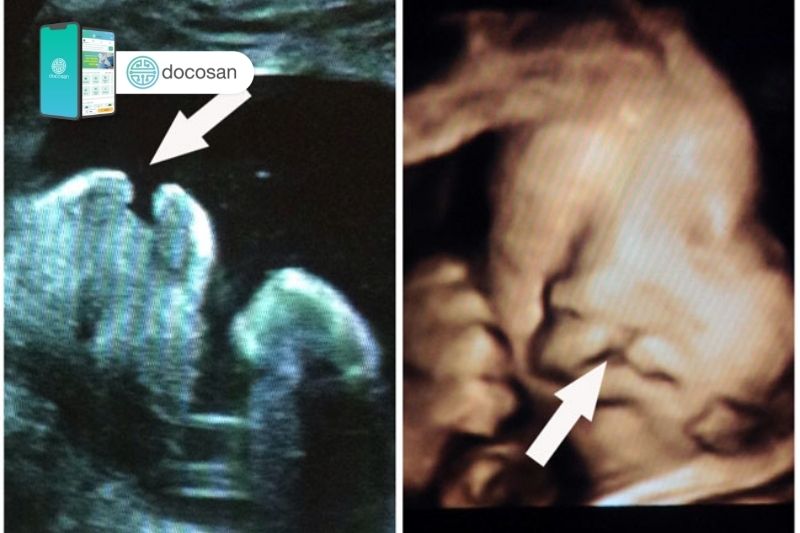

Siêu âm 4D là phương pháp có 3 chiều không gian và kết hợp thêm 1 chiều thời gian. Với công nghệ của máy siêu âm này thì các mẹ bầu có thể nhìn thấy mặt mũi, chân tay, các cử chỉ hành động của thai nhi một cách chân thật nhất. Nhờ đó, bác sĩ có thể phát hiện rõ được ra những dị tật thai nhi giai đoạn sớm, xác định nguy cơ bất thường để có những xử lý kịp thời đảm bảo cho sự phát triển của thai nhi và sức khỏe sản phụ.

Ngoài ra, việc thực hiện siêu âm 4D trong quá trình mang thai còn phụ thuộc vào sức khỏe của từng sản phụ và đánh giá nguy cơ của thai nhi mà bác sĩ sẽ chỉ định nên siêu âm vào thời điểm phù hợp. Siêu âm 4D cũng không có hại gì cho thai nhi mà tốt hơn thế nó còn giúp các bác sĩ phát hiện và chẩn đoán chính xác các dị tật như hở hàm ếch, các dị tật về não… và có những biện pháp xử lý kịp thời dựa trên kết quả siêu âm.